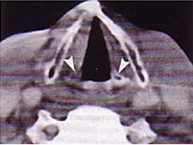

男,16歲,咽異物感6年,無咽部出血及吞咽障礙。檢查:舌根部中央有半球形腫物隆起,粘膜光滑,質地中等。頸部淋巴結不大:

11.MRI檢查結果如下圖,下一步最重要的檢查是  (    )

12.本患者最可能的診斷是  (    )

13.如果碘同位素檢查示舌根腫物有核素聚焦,而頸部無核素聚焦,正確的治療是  (    )

正確答案:11.C;12.C;13.A